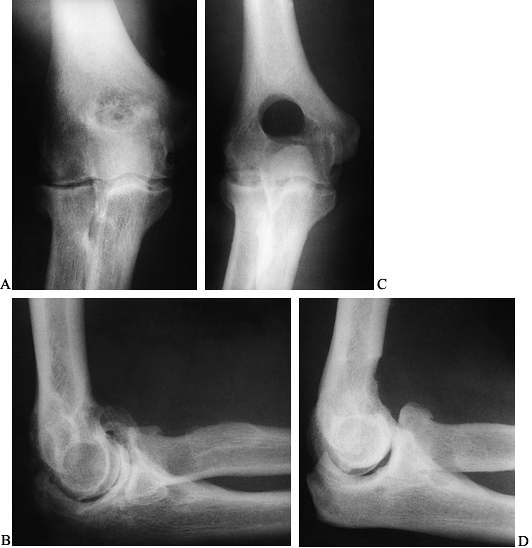

to 107° postoperatively (Fig. 102.5). Unlike

Figure 102.5.

Interposition arthroplasty: A 22-year-old woman with posttraumatic ankylosis of the elbow following a fracture of her distal humerus and forearm. A: Preoperative anteroposterior (AP) radiograph demonstrating a loss of joint space and heterotopic ossification. B: Preoperative lateral radiograph. C: Intraoperative appearance of the articular surface of the distal humerus with extensive loss of the articular cartilage of trochlea and absence of capitellum. D: Interposition graft secured in place on the distal humerus. E: Postoperative AP radiograph in Compass Elbow Hinge demonstrating joint distraction. F: Postoperative lateral radiograph in Compass Elbow Hinge showing correct articular alignment. G: One-year postoperative anterior posterior radiograph showing maintenance of joint space. H: One-year postoperative lateral radiograph demonstrating some postoperative resorption of the distal humerus. The patient achieved adequate functional outcome with motion from 30° to 130°, minimal pain, and no instability. |